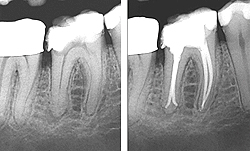

Часто причиною періодонтиту є неякісне лікування кореневих каналів; при рентгенографії добре видно уламки інструментів, залишених в каналі. Такі зуби часто підлягають екстракції, але замість видалення зубів можна спробувати їх вилікувати. Лікування полягає в тривалій терапії антисептиками і ультразвуком .

Тактика лікування загострень хронічного періодонтиту та ж, що і при лікуванні гострого гнійного періодонтиту . При цьому особлива увага приділяється дренированию каналів, відтік ексудату повинен бути вільним, це важливо в першу чергу при лікуванні багатокореневих зубів. Рентгенологічне дослідження визначає, навколо якого з каналів запальний процес більш виражений, саме цей кореневої канал потрібно краще дренувати.